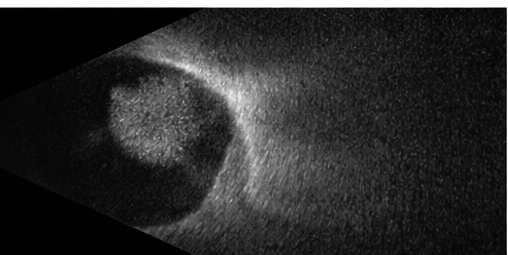

Multimodal imaging plays a pivotal role in establishing an accurate diagnosis and guiding management. Fundus photography allows documentation of lesion size, color, and progression over time, while optical coherence tomography (OCT) provides detailed cross-sectional imaging of the retina and choroid, enabling detection of subretinal fluid, retinal thickening, and macular involvement. B-scan ultrasonography typically demonstrates a highly reflective, acoustically solid lesion, which helps distinguish hemangiomas from choroidal melanomas. Fluorescein angiography further aids differentiation by revealing early hyperfluorescence with late staining, a pattern characteristic of vascular tumors [5]. In selected cases, indocyanine green angiography may offer additional diagnostic clarity.

Based on clinical appearance and imaging findings, a diagnosis of ocular hemangioma most consistent with a circumscribed choroidal hemangioma was made. Differential diagnoses considered included choroidal melanoma, metastatic lesion, and central serous chorioretinopathy; however, the lesion’s color, borders, and lack of associated risk features favored a benign vascular etiology.